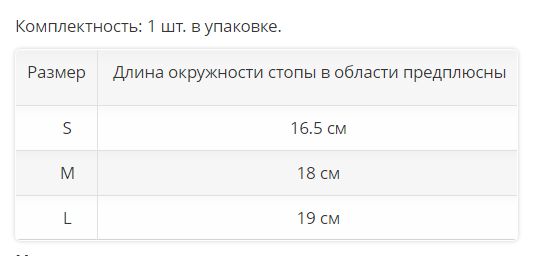

Комплектность: 1 шт. в упаковке.

| Размер |

Длина окружности стопы в области предплюсны |

| S | 16.5 см |

| M | 18 см |

| L |

19 см |